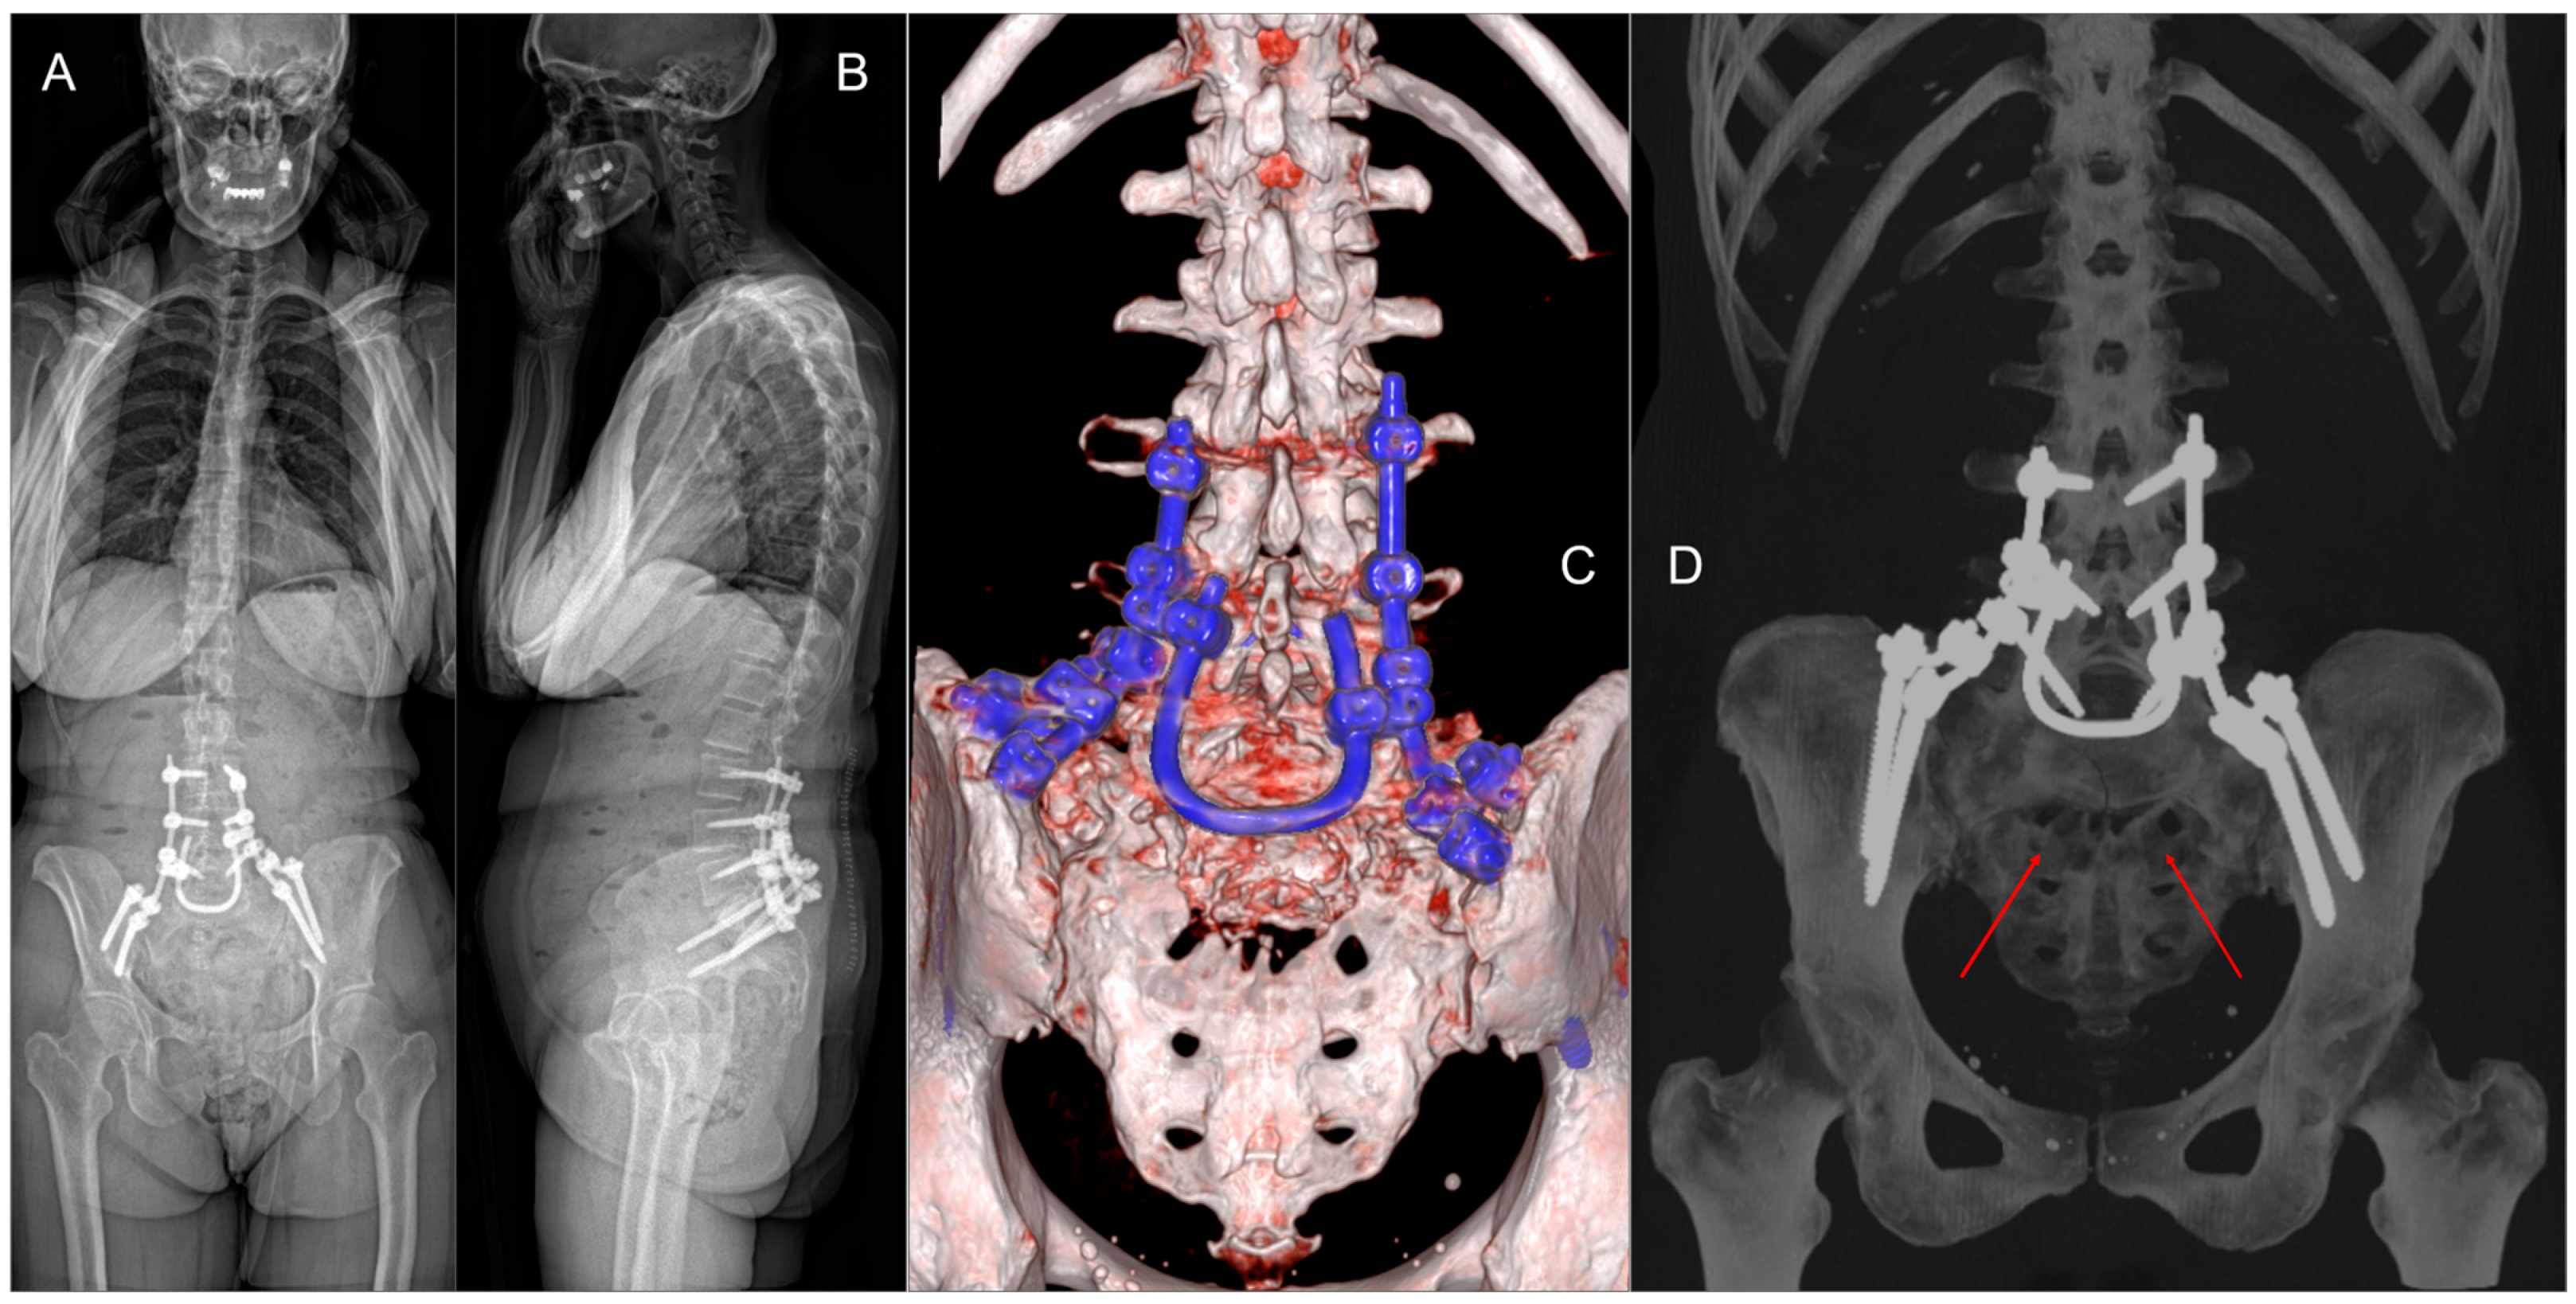

In June 2024, the patient presented to the Emergency Department with acute urinary retention, necessitating the placement of an indwelling urinary catheter. Subsequent MRI (Figure 1A–D) and CT scans confirmed progression of the sacral lesion with significant compression of sacral nerve roots. Based on the clinical and radiological findings, lumbopelvic fixation (LPF) was planned, including nerve root decompression and intralesional resection of the sacral lesion (Figure 1E). The surgical procedure had a total duration of 250 min, with intraoperative blood loss of 180 cc.

Figure 6. (A,B) Post-operative standing X-ray. (C,D) Six-month 3D CT scan reconstruction demonstrating the stability of the LPF and the residual sacral defect (red arrows).